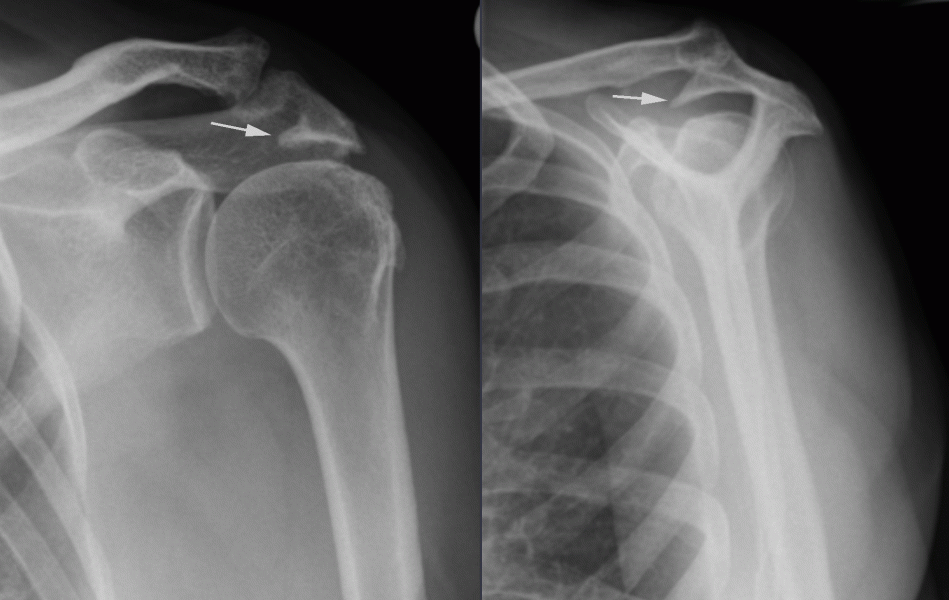

A diagnosis is made based on the history of a painful shoulder. Pain is usually intermittent and experienced when reaching overhead and often when lying on the shoulder at night. Examination shows pain with certain movements of the shoulder (such as lifting the arm above shoulder height) and on special rotator cuff tests. An X-ray may be useful to look at the shape of the acromion and the rest of the joint. An ultrasound scan may be performed to examine the state of the rotator cuff. Special imaging with an MRI scans is sometimes necessary.